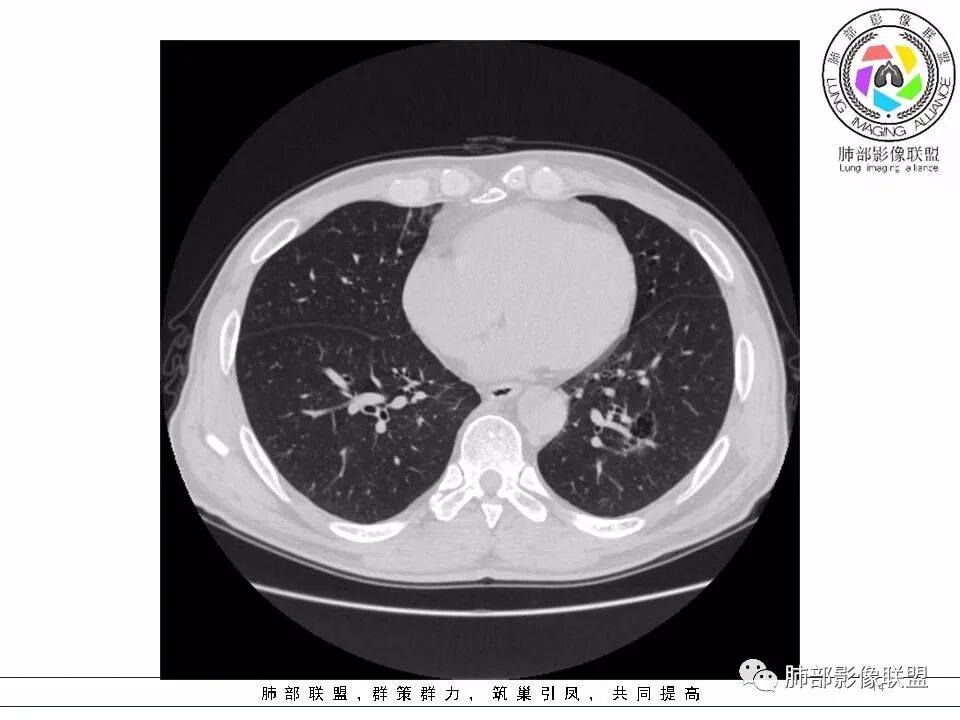

【每日晨读】黄色预警--警惕囊腔型的病变

2.左肺下叶外基底段囊腔样病灶,轮廓柔和,壁厚薄不均,见壁结节。内见分隔或脊状突起。腔内见血管穿行。

这是有“故事”的囊!

3.囊壁外环以磨玻璃影,边界较清楚。

1.囊腔壁厚薄不均,壁结节,内有分隔,其内有血管穿行,指向新生物。

2.临近有边界清楚磨玻璃影,指向腺癌。